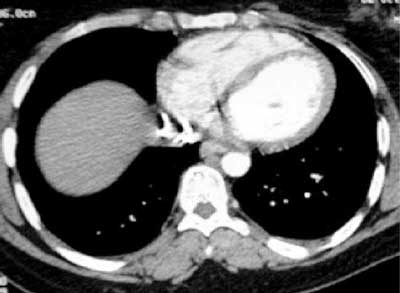

Figure 1

CT showing stent location in vena cava.